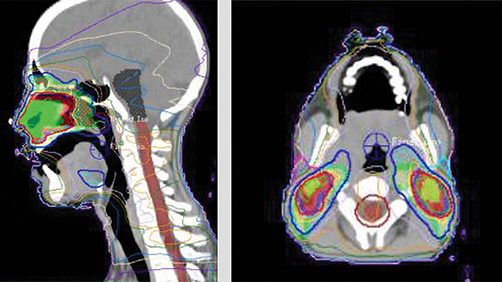

Radiación más quimioterapia para el linfoma nasal de células T/NK

Un ensayo clínico puede estandarizar el tratamiento para este cáncer infrecuente